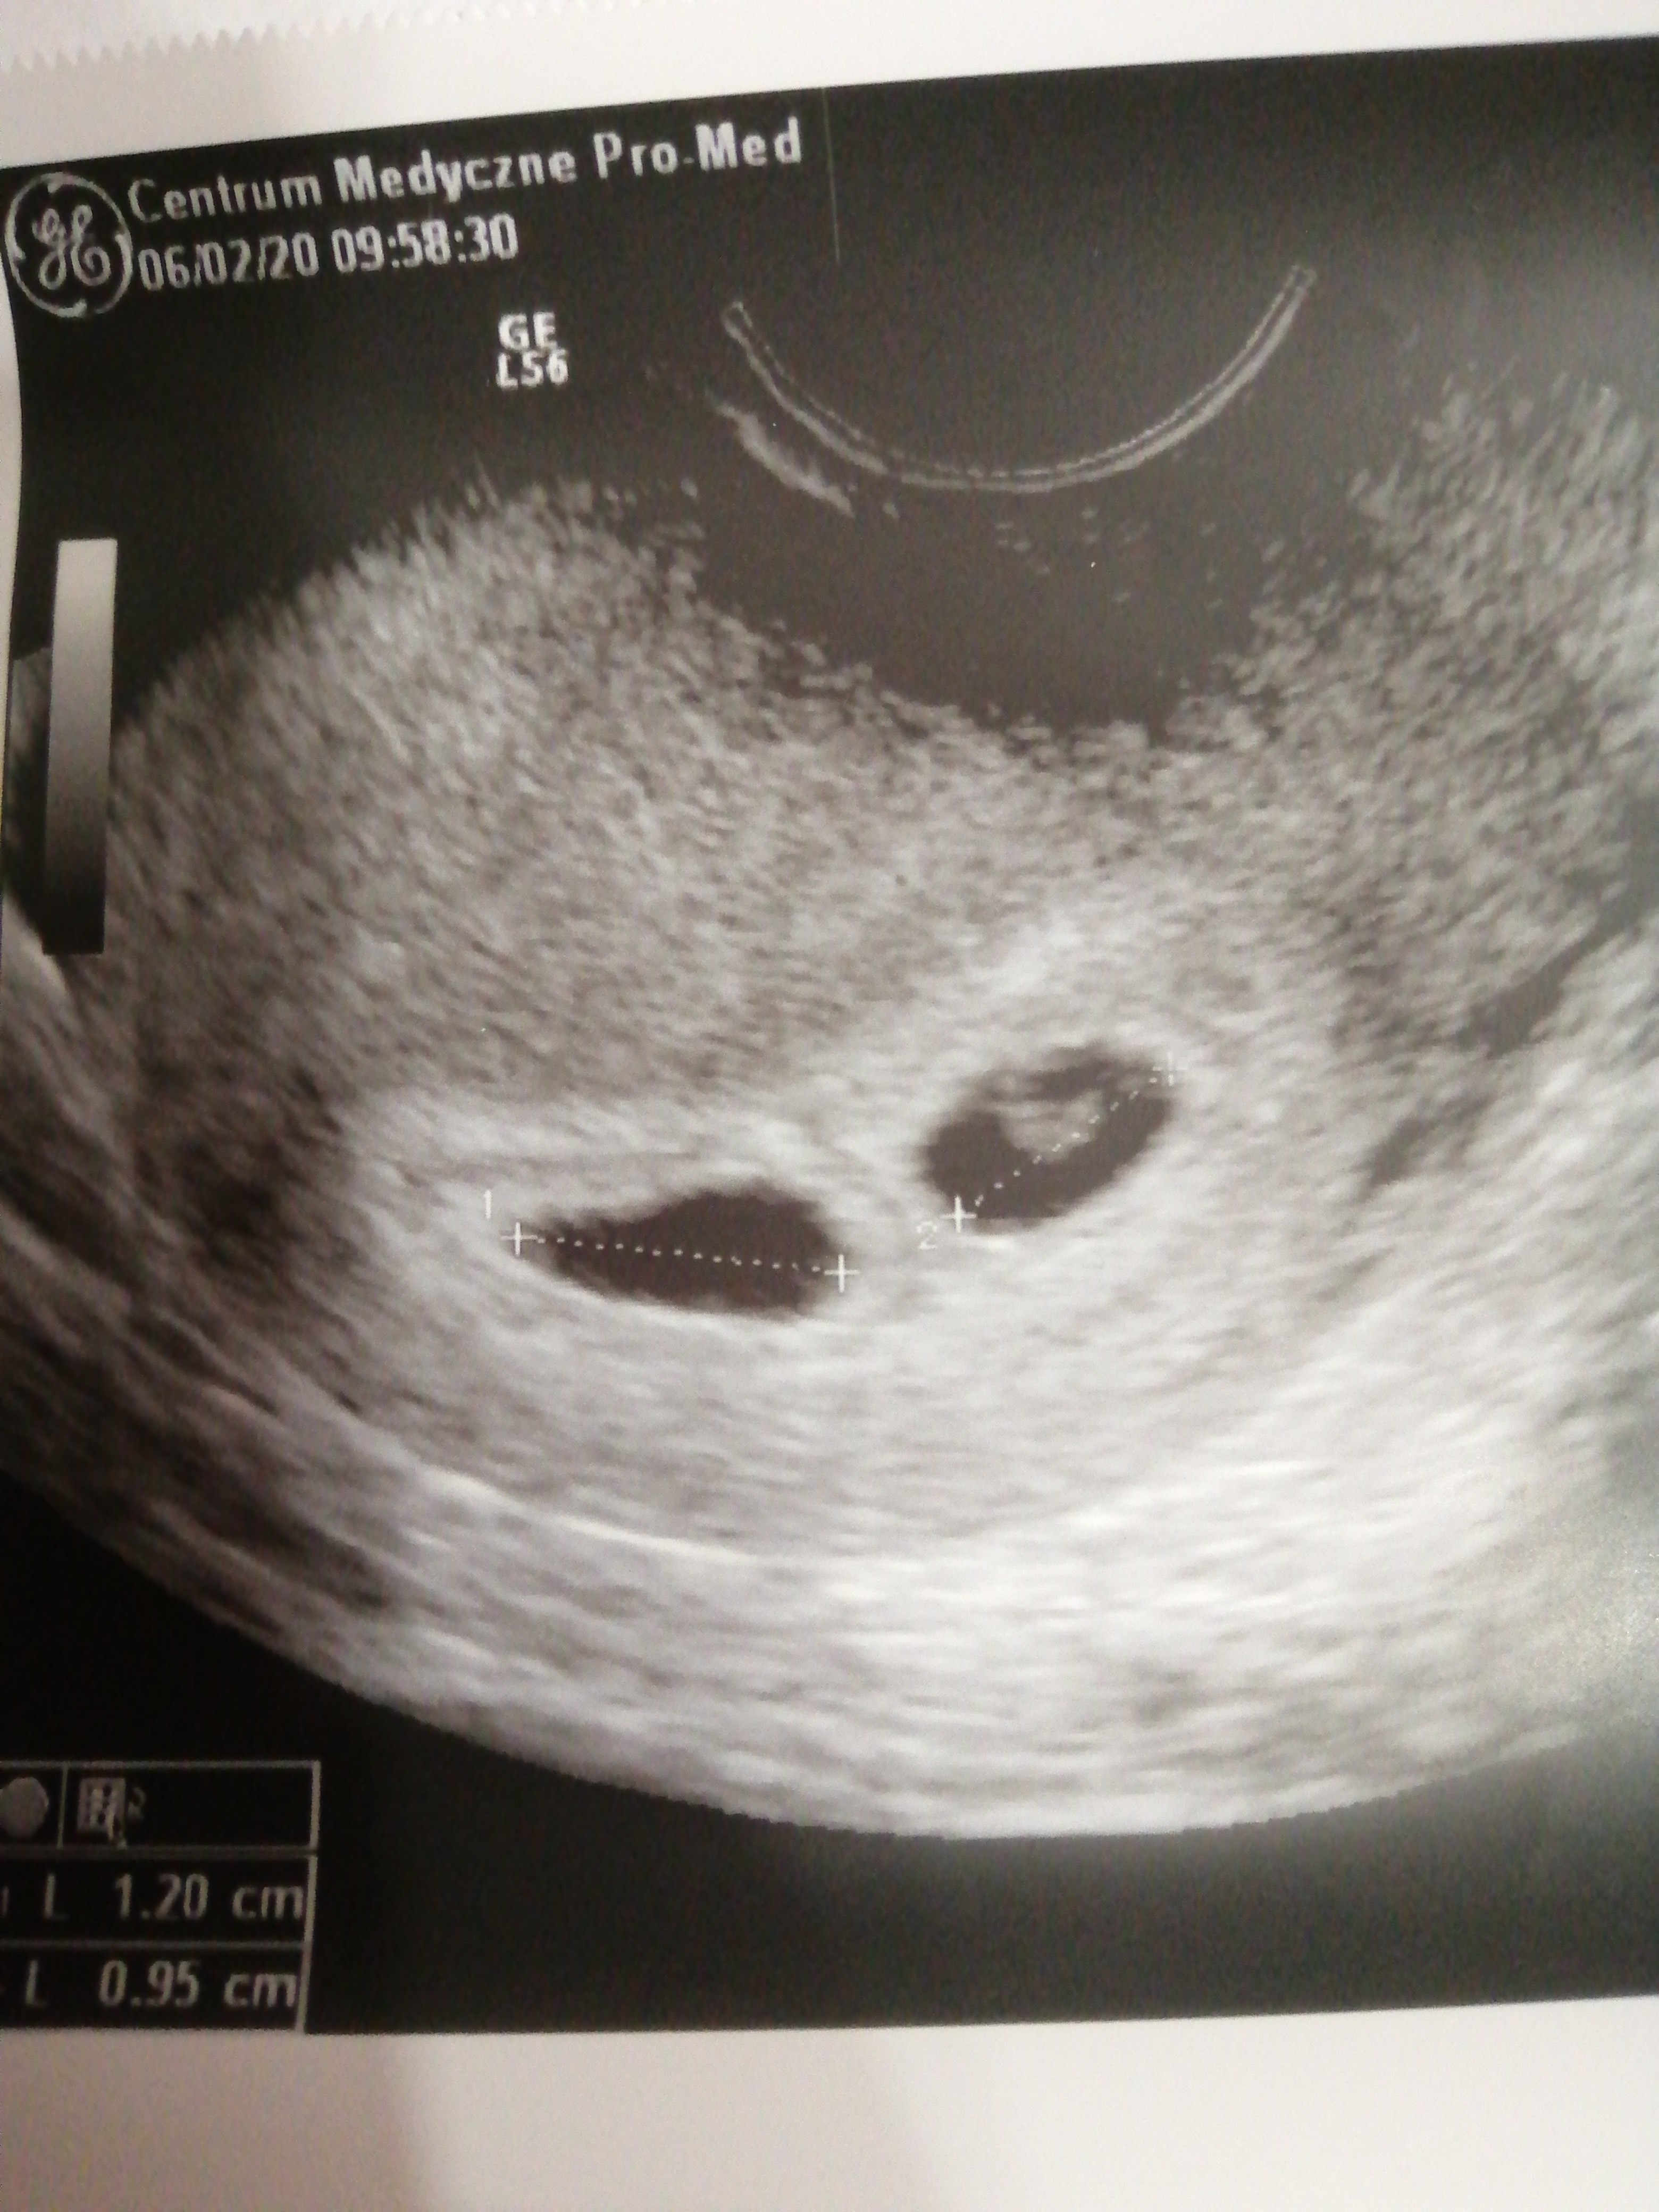

Hej. Ja po wizycie i usg. Poszłam tak wcześnie (5t+1) bo strasznie mnie boli i ciągnie brzuch. A jestem po jednym poronieniu.

No i..... okazało się że tak źle się czuję bo mam 2 pęcherzyki plodowe. Za 2tyg ponowna wizyta i zobaczymy czy będzie jedno czy bliźniaki 😉Zobacz załącznik 1076875